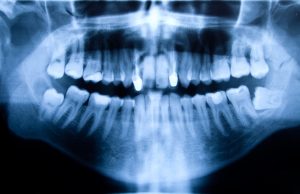

Решение об удалении зуба мудрости принимается индивидуально врачом-стоматологом-хирургом на основании рентгеновского снимка и клинической картины. Вот основные показания к удалению третьего моляра:

- Консультация врача и диагностика состояния пациента путём панорамного рентгенологического исследования.